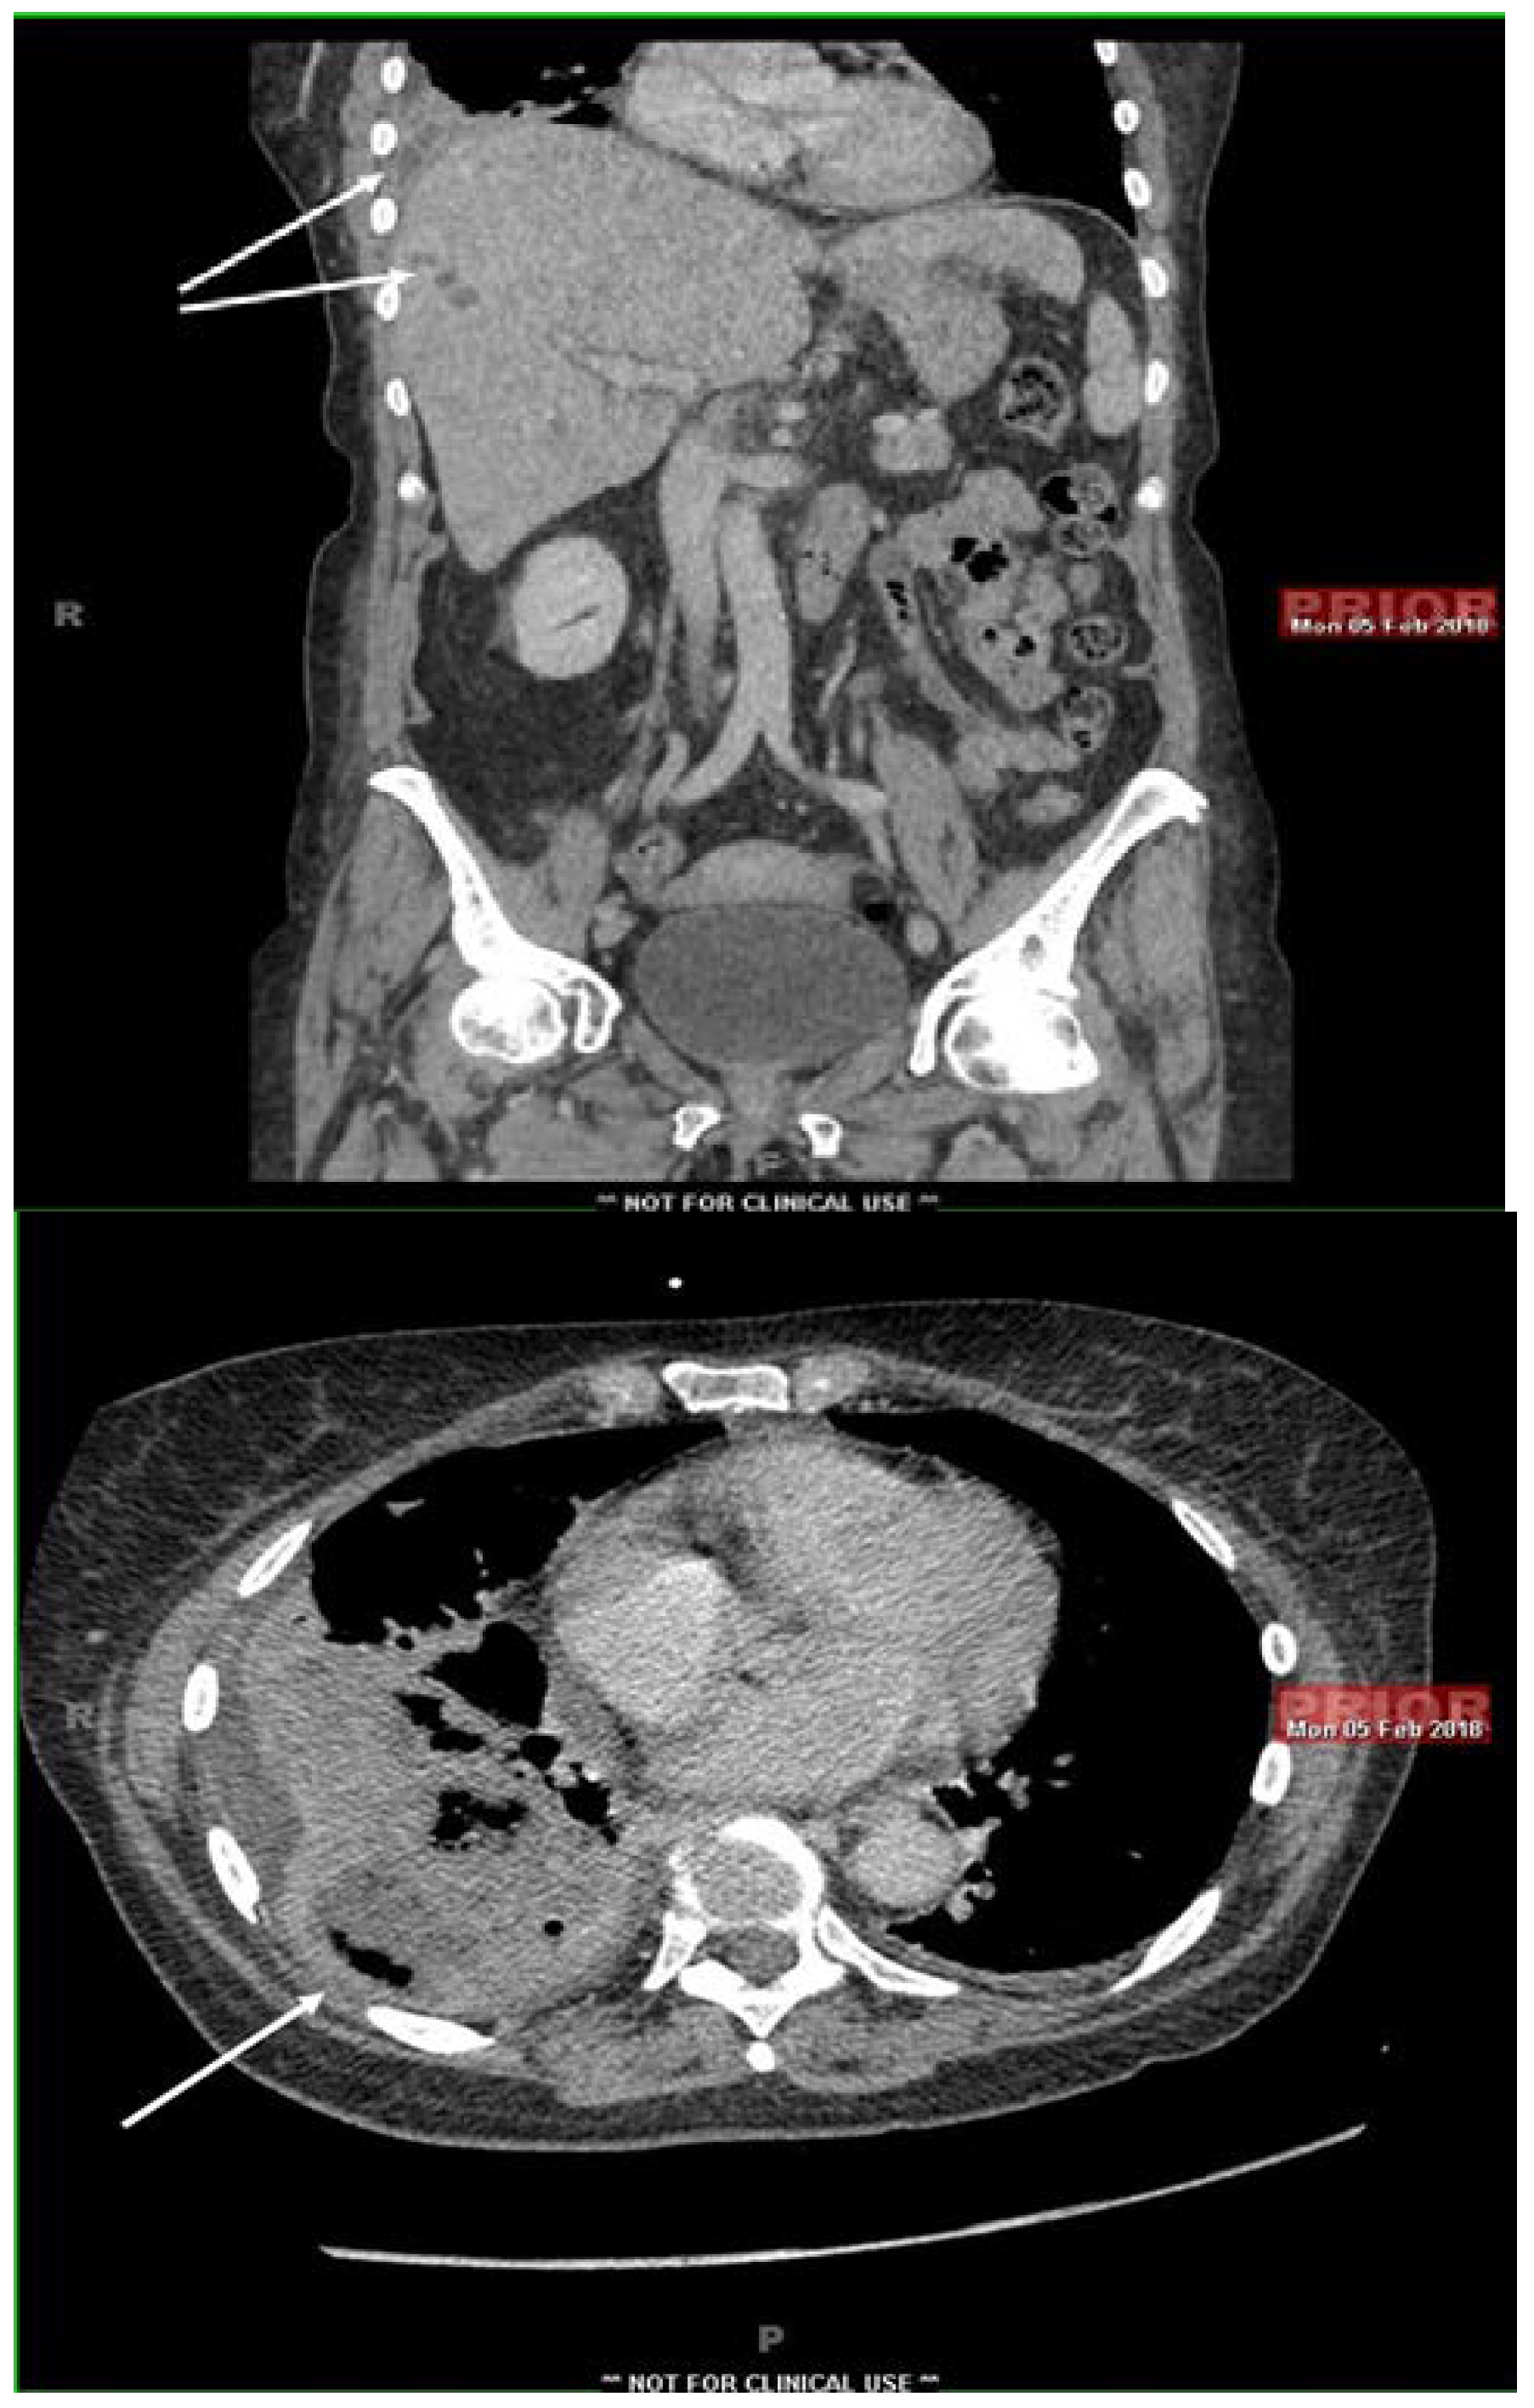

Fusobacterium nucleatum: A Cause of Subacute Liver Abscesses with Extensive Fibrosis Crossing the Diaphragm, Mimicking Actinomycosis